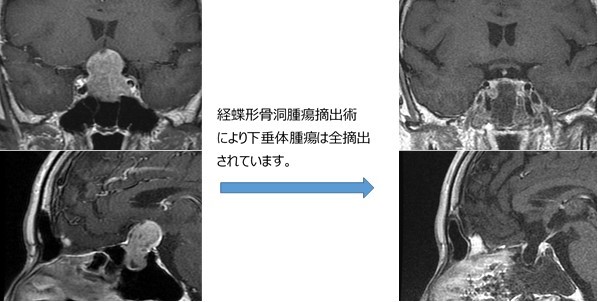

| 経蝶形骨洞 (けいちょうけいこつどう) |

2018 | 2019 | 2020 |

| 手術件数 | 17 | 18 | 14 |

下垂体腺腫(かすいたいせんしゅ)(下垂体腫瘍)をはじめとした下垂体近傍疾患の

治療を行っています。「間脳(かんのう)下垂体」は体を維持する真の中枢で、多彩な腫瘍が好発しますが、その病態や機能の理解は「内分泌学」に基づきます。

内分泌内科、小児科、放射線科や病理など関連各科と密に連携しながら、患者さんに最も適した診療を行っています。